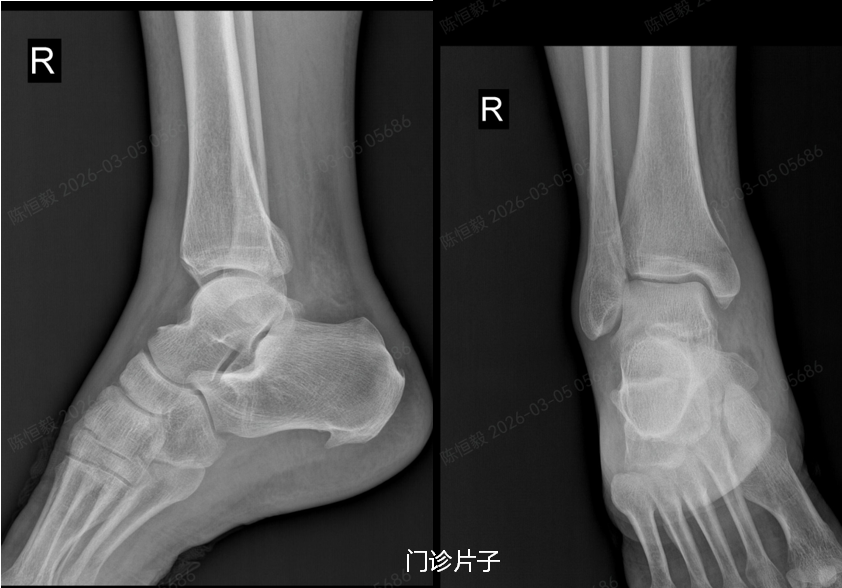

在北京积水潭医院郑州医院拍 X 光片后未见明显骨裂,王大爷更是觉得无需治疗,准备回家自行休养。

但接诊的足踝外科主任杨建义查看片子并仔细为其体格检查后,发现了异常,当即告知王大爷,其下胫腓部位大概率存在损伤,建议住院做进一步详细检查,排除隐匿性问题。

王大爷听从建议住院后,经完善体格检查及 CT 检查,最终确诊为复杂的 Maisonneuve 骨折:不仅存在下胫腓分离,还合并前踝 Chapute 结节撕脱骨折、后踝骨折、内踝骨折,同时伴有腓骨高位骨折。

普通 X 光片仅能判断是否存在明显骨折、脱位,对于下胫腓联合损伤、微小骨折、软骨损伤,以及 Maisonneuve 骨折涉及的腓骨高位骨折等隐匿性损伤,很难清晰显示。